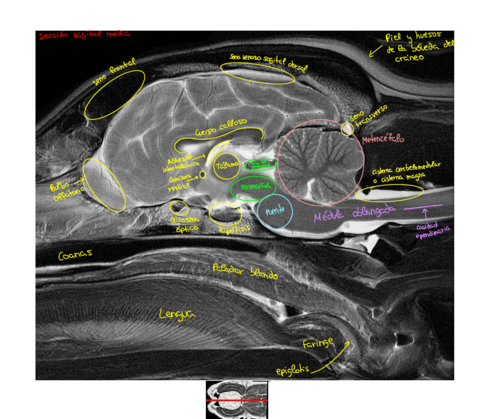

Apuntes - Imagenes-secciones-Resonancia-magnetica-cabeza-perro.pdf

Apuntes - Practicas-anatomia-Resonancia-magnetica.pdf